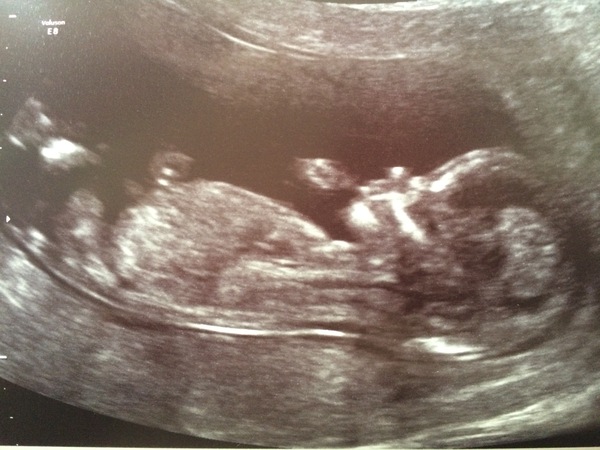

Hi all, another one checking in after scan today! 13+3 so due date now 11 December. Baby was so still and good for measurements and then started 'drinking' loads - lots of big gulps which was really sweet and funny to watch.

So exciting to see all these pictures - we're well on our way now and all feeling very real.

Had my scan today! All fine and been moved to 17th December, yay! Baby wasn't very cooperative but got a few photos... This ones like a crab Grin

loosey that's amazing, you can see all the fingers!!

So many lovely photos! We got our Harmony results back today - all low risk and joining TEAM BLUE!